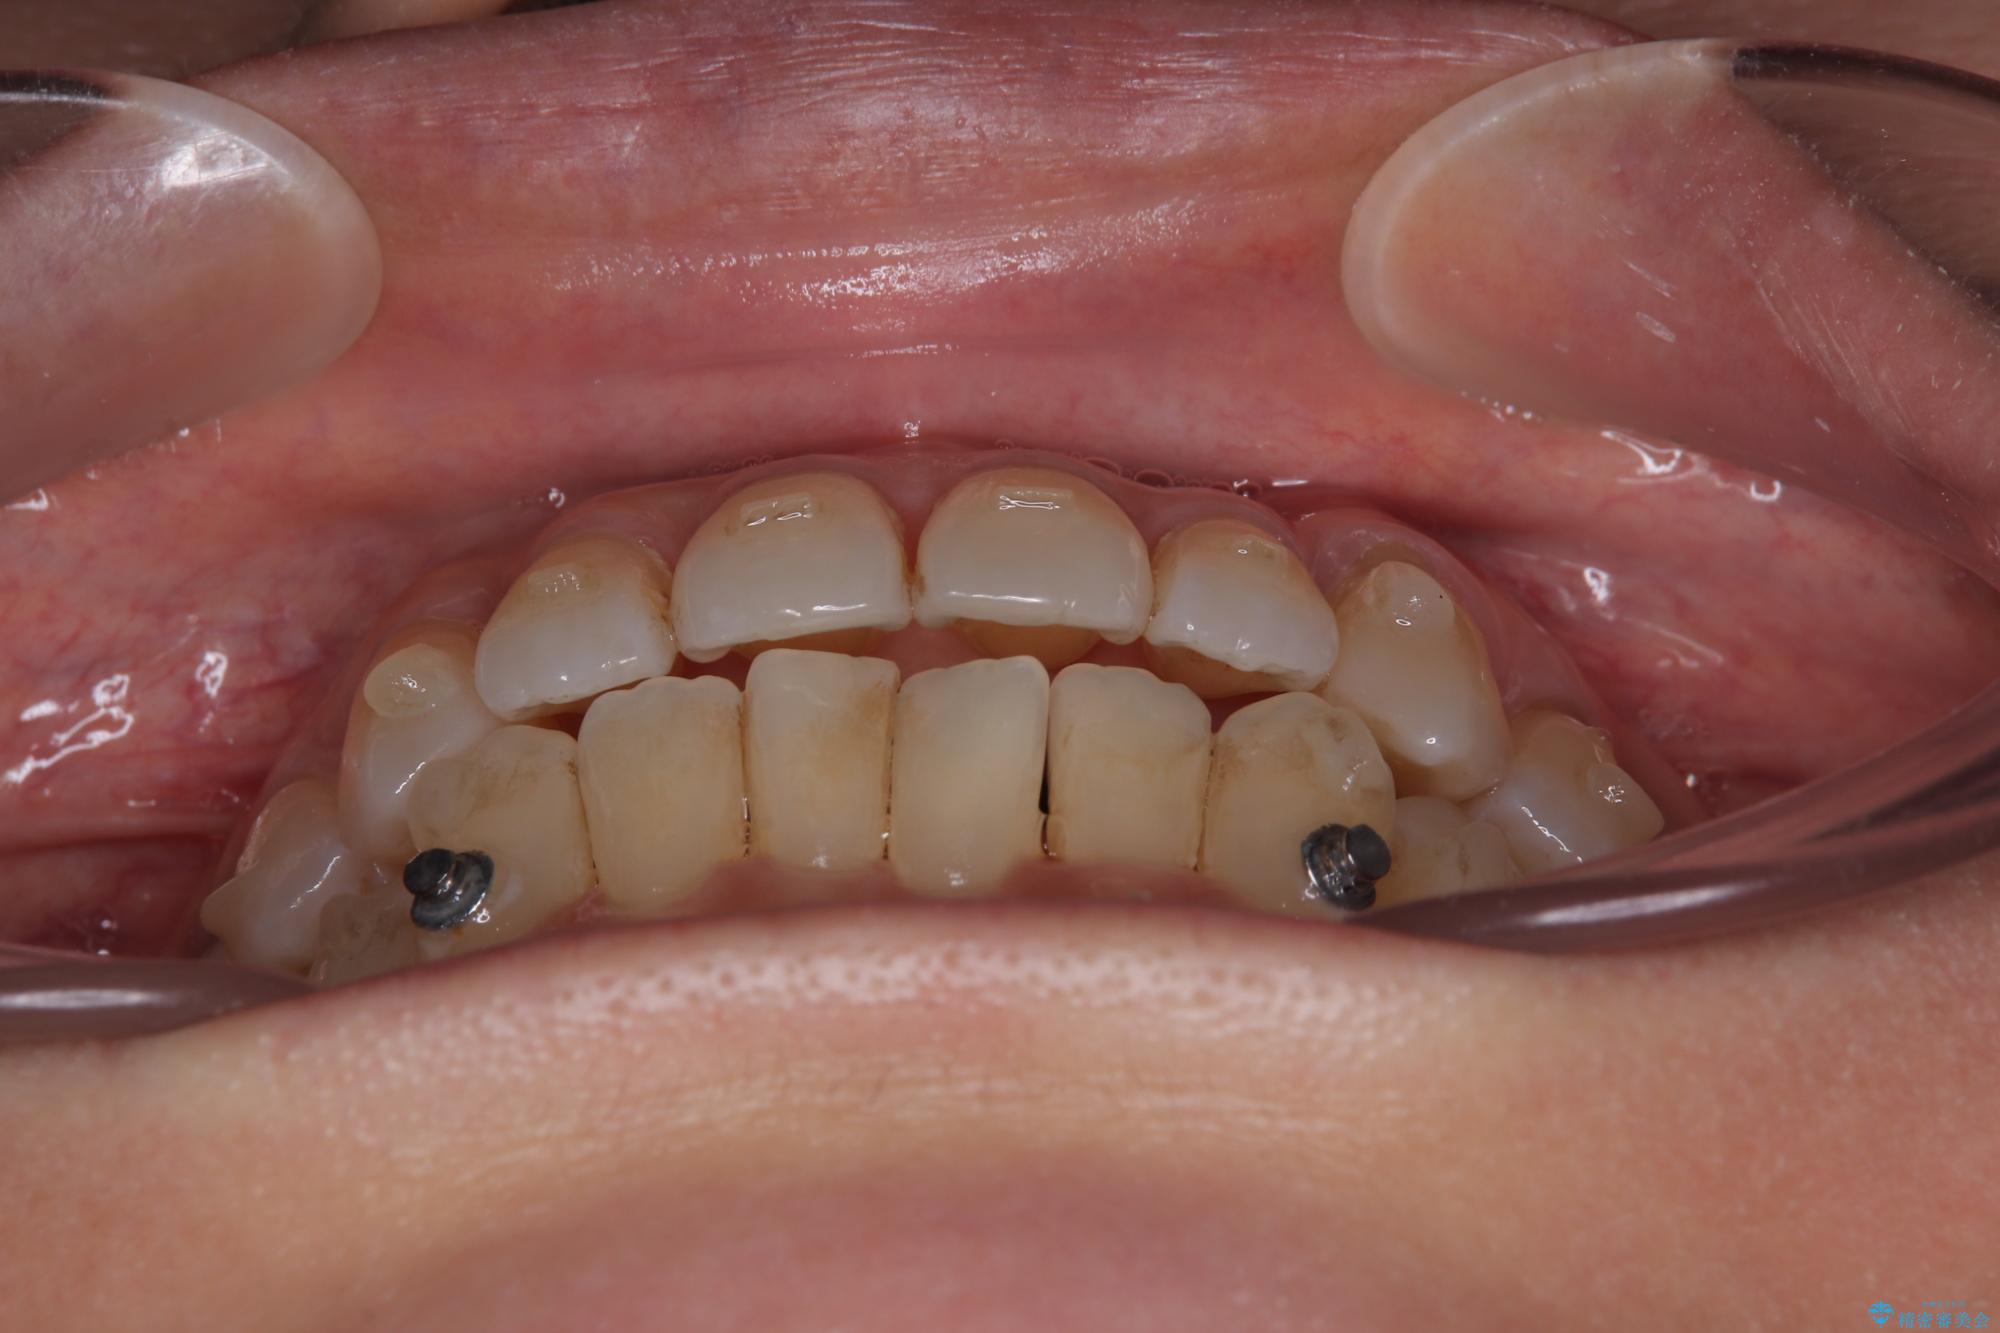

- 前歯のデコボコや八重歯を治したいとのことで来院された患者様です。

受け口傾向の骨格であり、前歯はクロスバイトまたは切端咬合となっており、下顎を中心に歯列全体の後方移動を行い、IPR(歯と歯の間を削る)によってデコボコが解消するように設計し、インビザラインにより治療を行うこととしました。

受け口傾向のインビザライン矯正は比較的治療を行いやすいため、きれいに仕上げることができました。舌の突出癖が顕著であったため、改善のためのトレーニングをしっかりと行っていただきました。